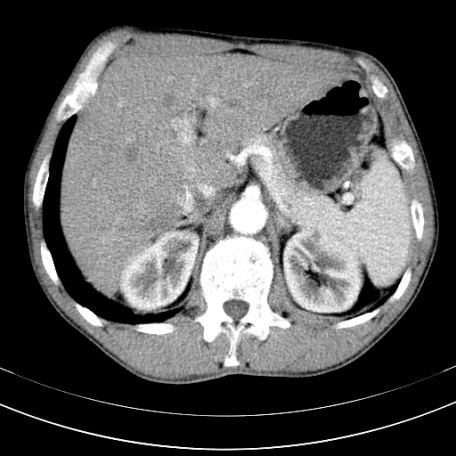

标题: CT21441:男55岁,上腹部胀痛半年余,请老师们看看是后腹膜淋巴 [打印本页]

标题: CT21441:男55岁,上腹部胀痛半年余,请老师们看看是后腹膜淋巴

腹主动脉右侧有一个,有肿瘤病史吗?

腹膜后淋巴结肿大,原因待查。

支持   腹膜后淋巴结肿大,原因待查